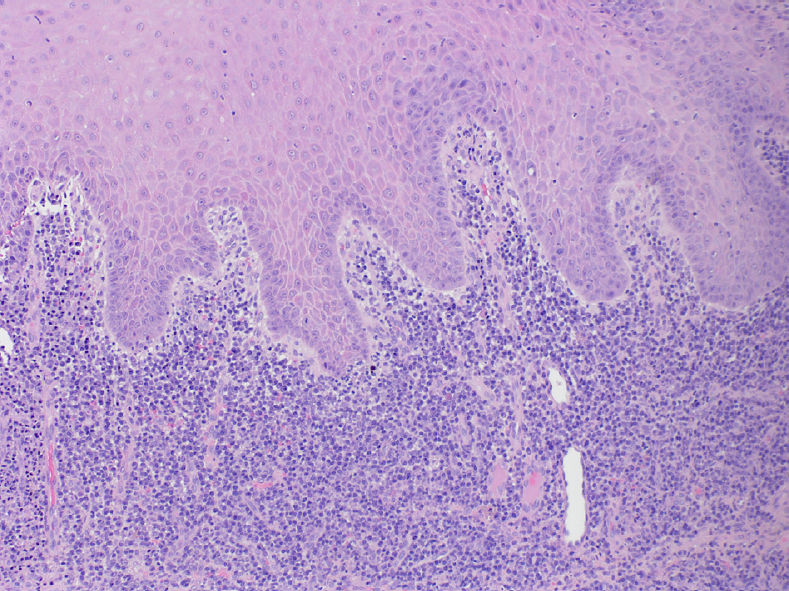

Была выполнена инцизионная биопсия. Гистологическое исследование выявило выраженную инфильтрацию соединительной ткани преимущественно плазматическими клетками, гиперплазию эпителия с сохранённым нормальным типом созревания.

Фото 2. Микроскопическое исследование выявило выраженную инфильтрацию хроническими воспалительными клетками, преимущественно плазматическими клетками (окраска гематоксилином и эозином, увеличение ×100). Эпителий гиперплазирован, с сохранённым нормальным типом созревания

Гистологически преобладание плазматических клеток в составе хронического воспалительного инфильтрата позволяет заподозрить сифилис. Однако окончательный диагноз требует сопоставления клинической картины, социального и медицинского анамнеза пациента, гистологических данных и результатов серологического обследования. Сифилис относится к заболеваниям, подлежащим обязательной регистрации, и после установления диагноза должен быть сообщён в местные органы здравоохранения.